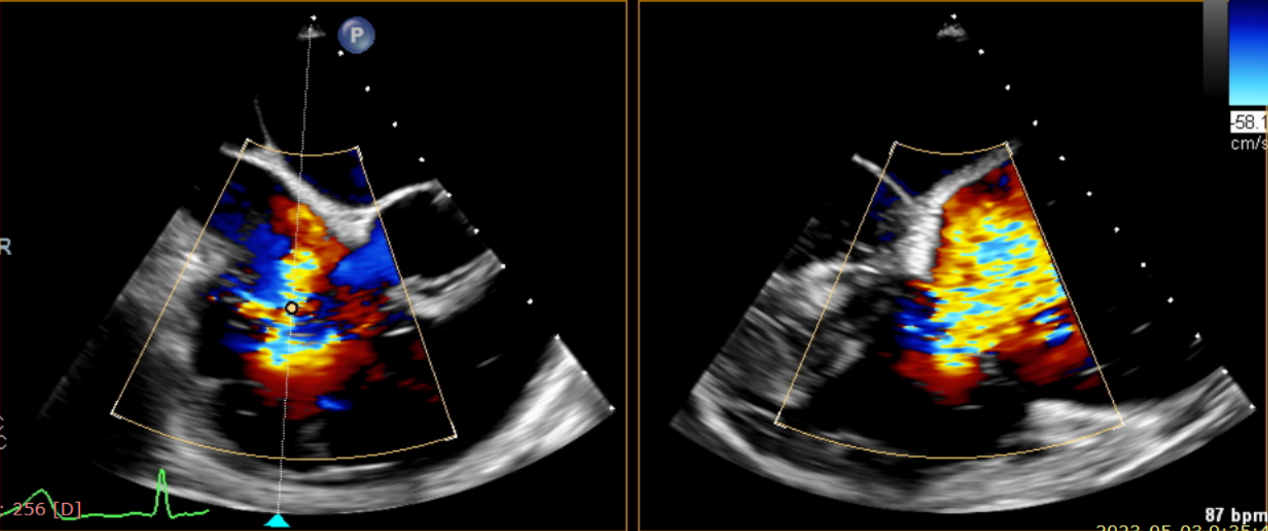

術中輸送器在超聲引導下調整位置